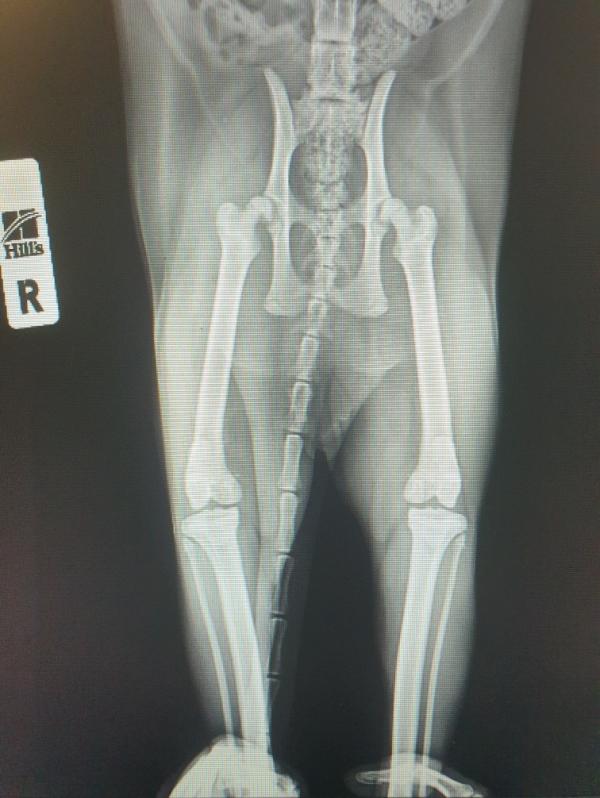

Может кто разбирается и мне повезет. Это снимок кота. У него назначена операция на бедро правой лапы. Я была в шоке и ничего не поняла. Что у него там не так. Сижу теперь дома смотрю снимок и как дура. Может кто понимает и обьведет мне это место.🙏🌷